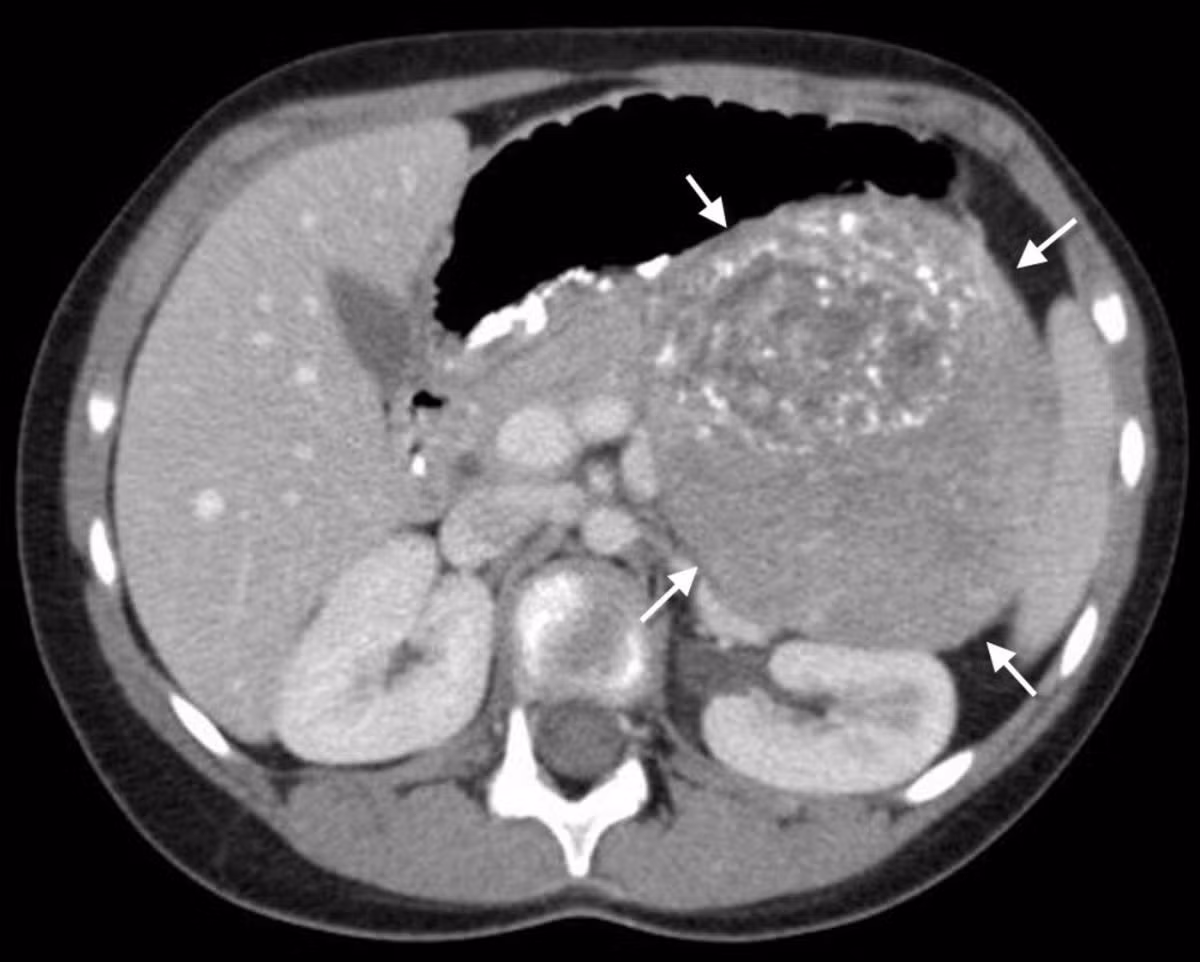

Daniel Carter, hiện sống ở Hull đã nhăn nhó vì đau bụng trong hàng tháng trời nhưng các bác sĩ ở bệnh viện Calpol chỉ cho rằng cậu bé bị táo bón. Chỉ khi thấy con mình nằm bất tỉnh trên sàn nhà, gia đình mới vội vã đưa bé đi cấp cứu. Kết quả chụp cắt lớp cho thấy cậu bé bị một khối u ác tính.

Ca phẫu thuật kéo dài 4 tiếng nhưng chỉ loại bỏ được một phần khối u. Đây là u nguyên bào thần kinh, ban đầu xuất phát từ vùng ngực nhưng sau di căn xuống đến xương sống. Vì vậy, ca phẫu thuật cắt bỏ khối u đã làm ảnh hưởng đến cột sống khiến cậu bé không đi được và phải ngồi xe lăn.

U nguyên bào thần kinh là một dạng ung thư hiếm gặp ở trẻ em, thường xuất hiện ở một trong hai tuyến thượng thận trong bụng hoặc trong các tế bào thần kinh chạy dọc theo xương sống. Ung thư có thể di căn đến các tế bào xung quanh như tủy, xương, bạch huyết, gan và da. Bệnh thường được phát hiện ở trẻ nhỏ dưới 5 tuổi nhưng phần lớn đều không xác định được nguyên nhân.